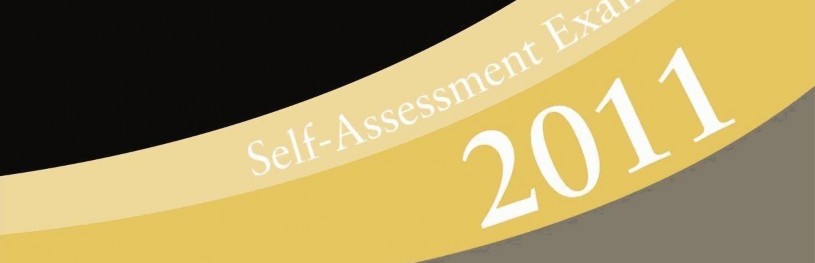

Question 1 A 30-year-old man has a painful ankle mass. Radiographs are seen in Figures 1a and 1b, and MRI scans are seen in Figures 1c and 1d. What is the most likely diagnosis?

Question 1 A 30-year-old man has a painful ankle mass. Radiographs are seen in Figures 1a and 1b, and MRI scans are seen in Figures 1c and 1d. What is the most likely diagnosis?

DISCUSSION: The calcified loose bodies shown on the imaging studies are characteristic of synovial chondromatosis. Pigmented villonodular synovitis and lipoma arborescens do not show calcifications. Synovial sarcoma and synovial hemangioma can mineralize but they tend to be more diffuse, and not associated with loose bodies. Synovial sarcoma is rarely intra-articular. Preferred Res # 1 is 4.

DISCUSSION: The calcified loose bodies shown on the imaging studies are characteristic of synovial chondromatosis. Pigmented villonodular synovitis and lipoma arborescens do not show calcifications. Synovial sarcoma and synovial hemangioma can mineralize but they tend to be more diffuse, and not associated with loose bodies. Synovial sarcoma is rarely intra-articular. Preferred Res # 1 is 4.